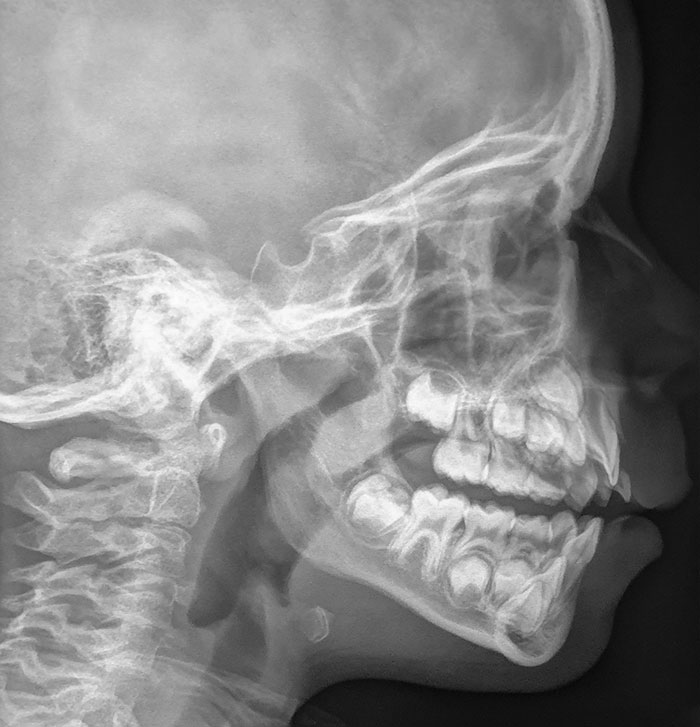

I Have A Rare Disorder Called Cleidocranial Dysotosis. Got My First Dental X-Ray Today And I Have A Lot Of Extra Teeth